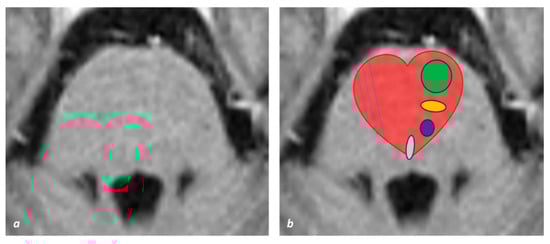

2. Neuroanatomical Issues

2.1. Corticospinal Tract in the Brainstem

2.2. General Vascular Organization and Territories of the Brainstem